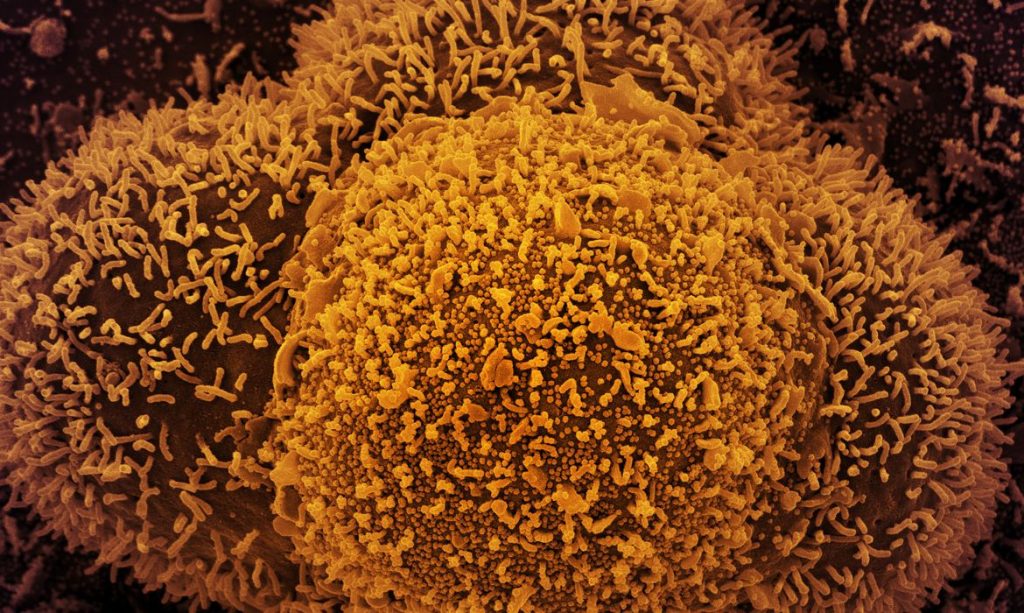

Dados fazem parte de boletim epidemiológico do Ministério da Saúde

Agência Brasil — O Brasil registrou, desde o início da pandemia, 655.249 mortes por covid-19, segundo o boletim epidemiológico divulgado hoje (14) pelo Ministério da Saúde. O número total de casos confirmados da doença é de 29.380.063.